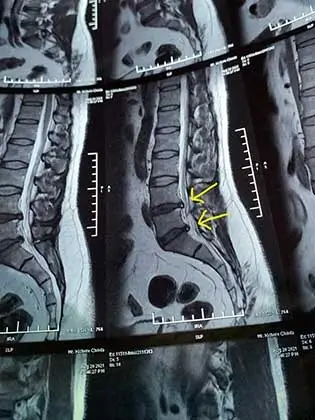

Cervical Spondylosis, Sciatica & Slip disc surgeries can be avoided in 80% cases.

Slip Disc

A slipped disc, or herniated disc, occurs when the soft inner material of a spinal disc protrudes through the tough outer layer, often causing pain and nerve compression.

Briefly describing your health issue. If available, share your medical reports (X-ray, MRI, etc.). Our team will contact you promptly to discuss the next steps.